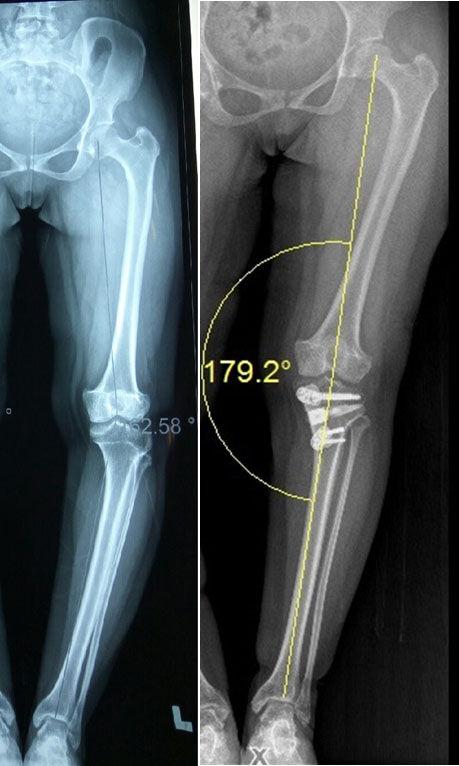

A 17-year-old Iraqi girl with a metabolic abnormality presents with deformity and pain in the knee. She has gross varus and the difficulty to walk.

Deformity correction with Osteotomy

If adequate time is not available for a growth modulation surgery (typically girls stop growing at 14 and boys at 16 years), then we will have to perform an operation called Osteotomy where the bone is broken. The deformity is corrected acutely, and proper mechanical alignment obtained.

Case illustration

A 17-year-old Iraqi girl with a metabolic abnormality presents with deformity and pain in the knee. She has gross varus and the difficulty to walk.